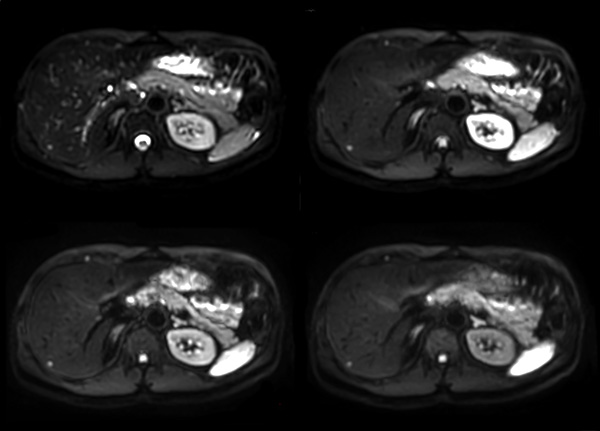

Axial mDIXON (W, IP, OP, F)